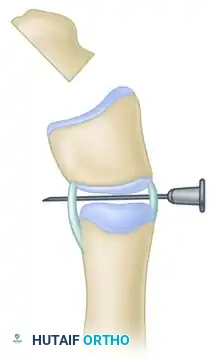

Step D: Orientation for Osteotomy

Place a hypodermic needle (e.g., 22-gauge) transversely across the interphalangeal joint. This serves as a critical visual and radiographic marker to orient the subsequent transverse osteotomy parallel to the joint line.

Step E: Completion of the Osteotomy

Using a fine oscillating saw or sharp osteotome, complete the transverse osteotomy through the delta phalanx, utilizing the needle as a guide to ensure the cut is perfectly parallel to the joint surface.